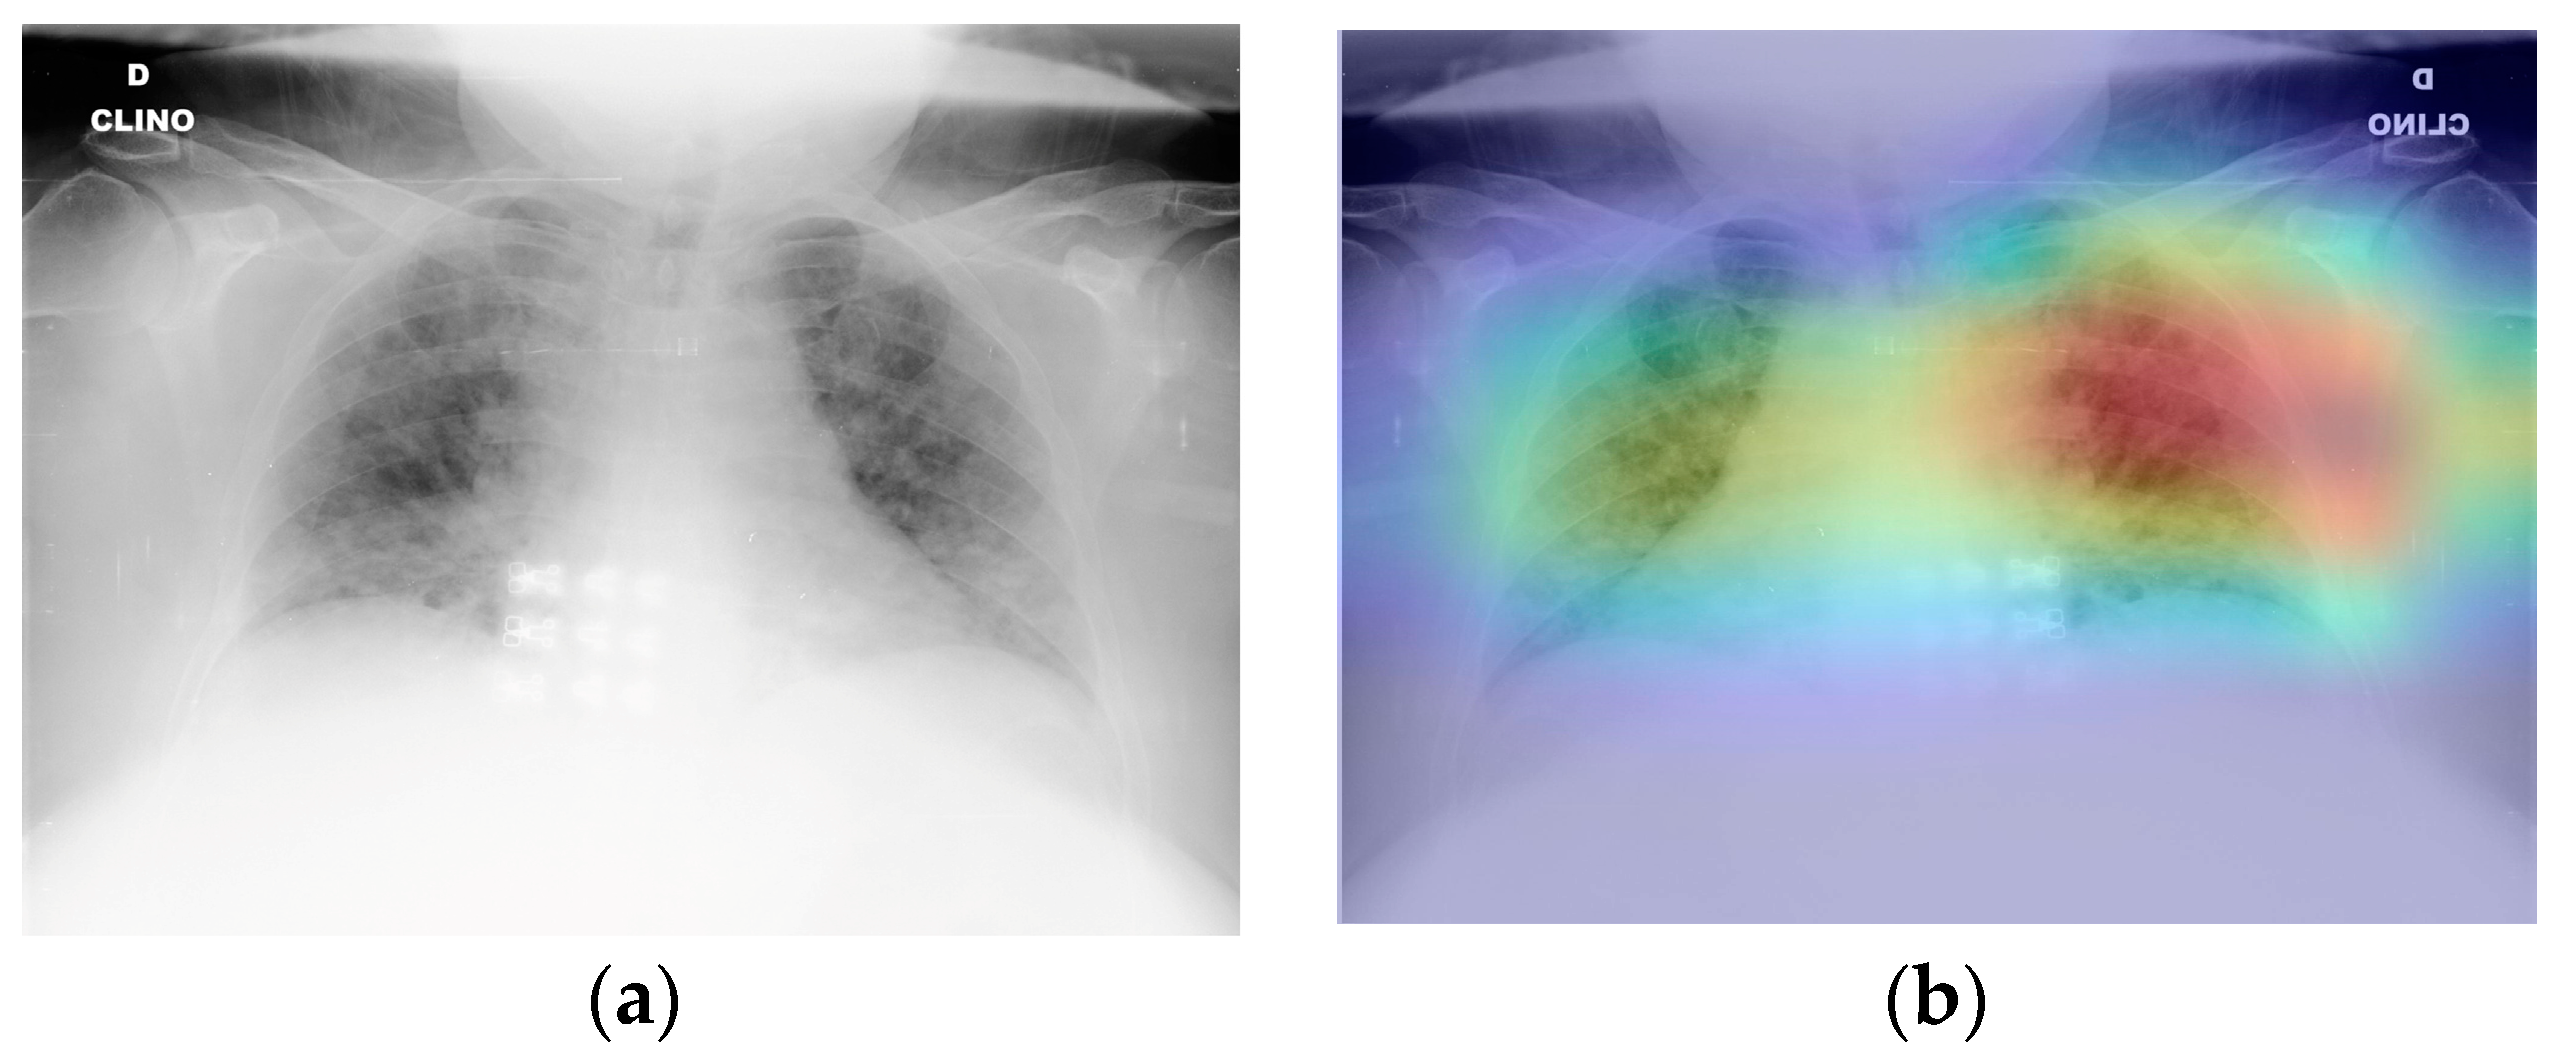

Enhancing the interpretability of deep learning models is crucial in numerous medical imaging applications. Selvaraju et al. [25] have developed the Gradient Weighted Class Activation Mapping (Grad-CAM) technique, which offers a clear and interpretable representation of deep learning models. The Grad-CAM technique generates visual explanations for neural networks with strong connections, providing insights into the model’s behaviour during detection or prediction tasks. Grad-CAM based colour visualisation approach [26] is used to accurately interpret the detection of radiology images and determine the subsequent course of action.

Figure 9 depicts the application of Grad-CAM on a trained model to visualise the impact of COVID-19 on an infected individual. The original COVID-19 image (a) and the class activation map for COVID-19 (b) are shown to highlight the areas of interest in our model’s prediction. These areas are represented by high-intensity visuals in blue and green. The utilisation of Grad-CAM in this study amplifies the interpretability and explanatory capacity of the proposed deep learning model.